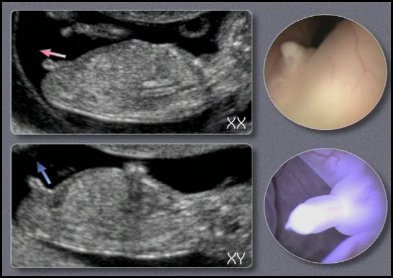

Echographie Determiner Le Sexe Du Bebe

Comment Connaitre Le Sexe De Bebe D Apres Son Echographie Happy And Baby

Sexe De Bebe Decryptez Votre Echographie Magicmaman Com